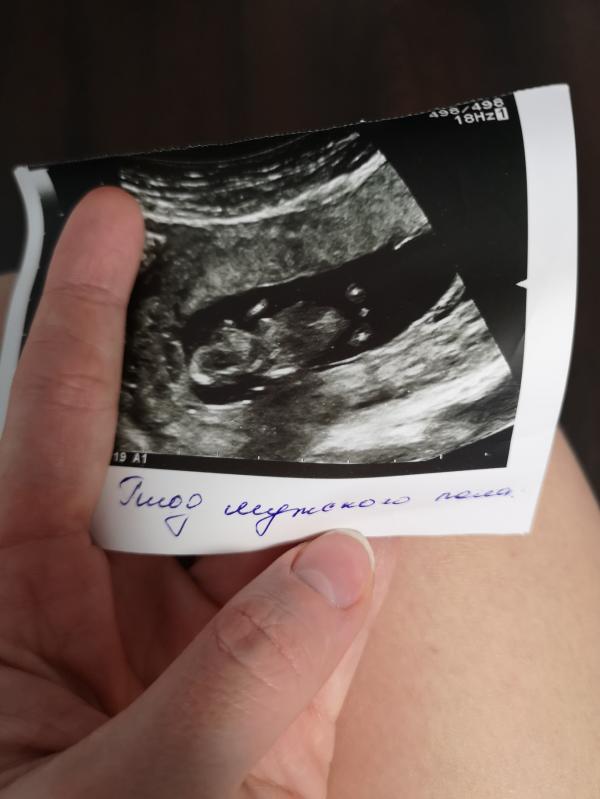

Красавица дочка есть, сыночек почти есть 😍😍😍😍😍😍Пазл практически собран))))) Вот рожу и моя детородная функция на этой земле будет закончена 😂 Как я ждала этой фразы "могу вас поздравить, у вас будет СЫН" 😭

Поздравляю ! Я тоже поверить не могла , в 16 недель пошла к Титаренко, ещё раз пол узнать , раза три переспросила а точно , точно там мальчик 😂 , мальчик да 🤣 , потом он сделал снимок обвёл его достоинство и написал 100 %men 🤣

Я тоже три раза переспросила точно ли там девочка, счастью своему поверить не могла)) только в этот раз мне нигде не написали, что плод женского пола 😄 в первый раз узнавала уже на 22 неделе , там прямо в заключении УЗИ написали ))